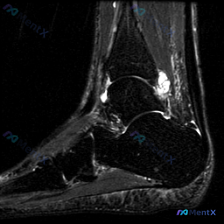

看到一份很有代表性的踝关节MRI影像,整理了资料和分析思路分享给大家。 病例影像基本信息 这是一份踝关节矢状位T2加权像(T2WI),先给大家说下客观观察到的结果: 1. 解剖结构显示清晰:可以看到胫骨远端、距骨、跟骨、足舟骨及部分跖骨 2. 核心异常发现: - 胫距关节腔前方、后方可见明显T2高信...